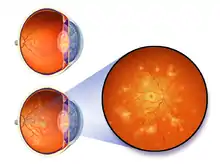

| Image of fundus showing scatter laser surgery for diabetic retinopathy | |